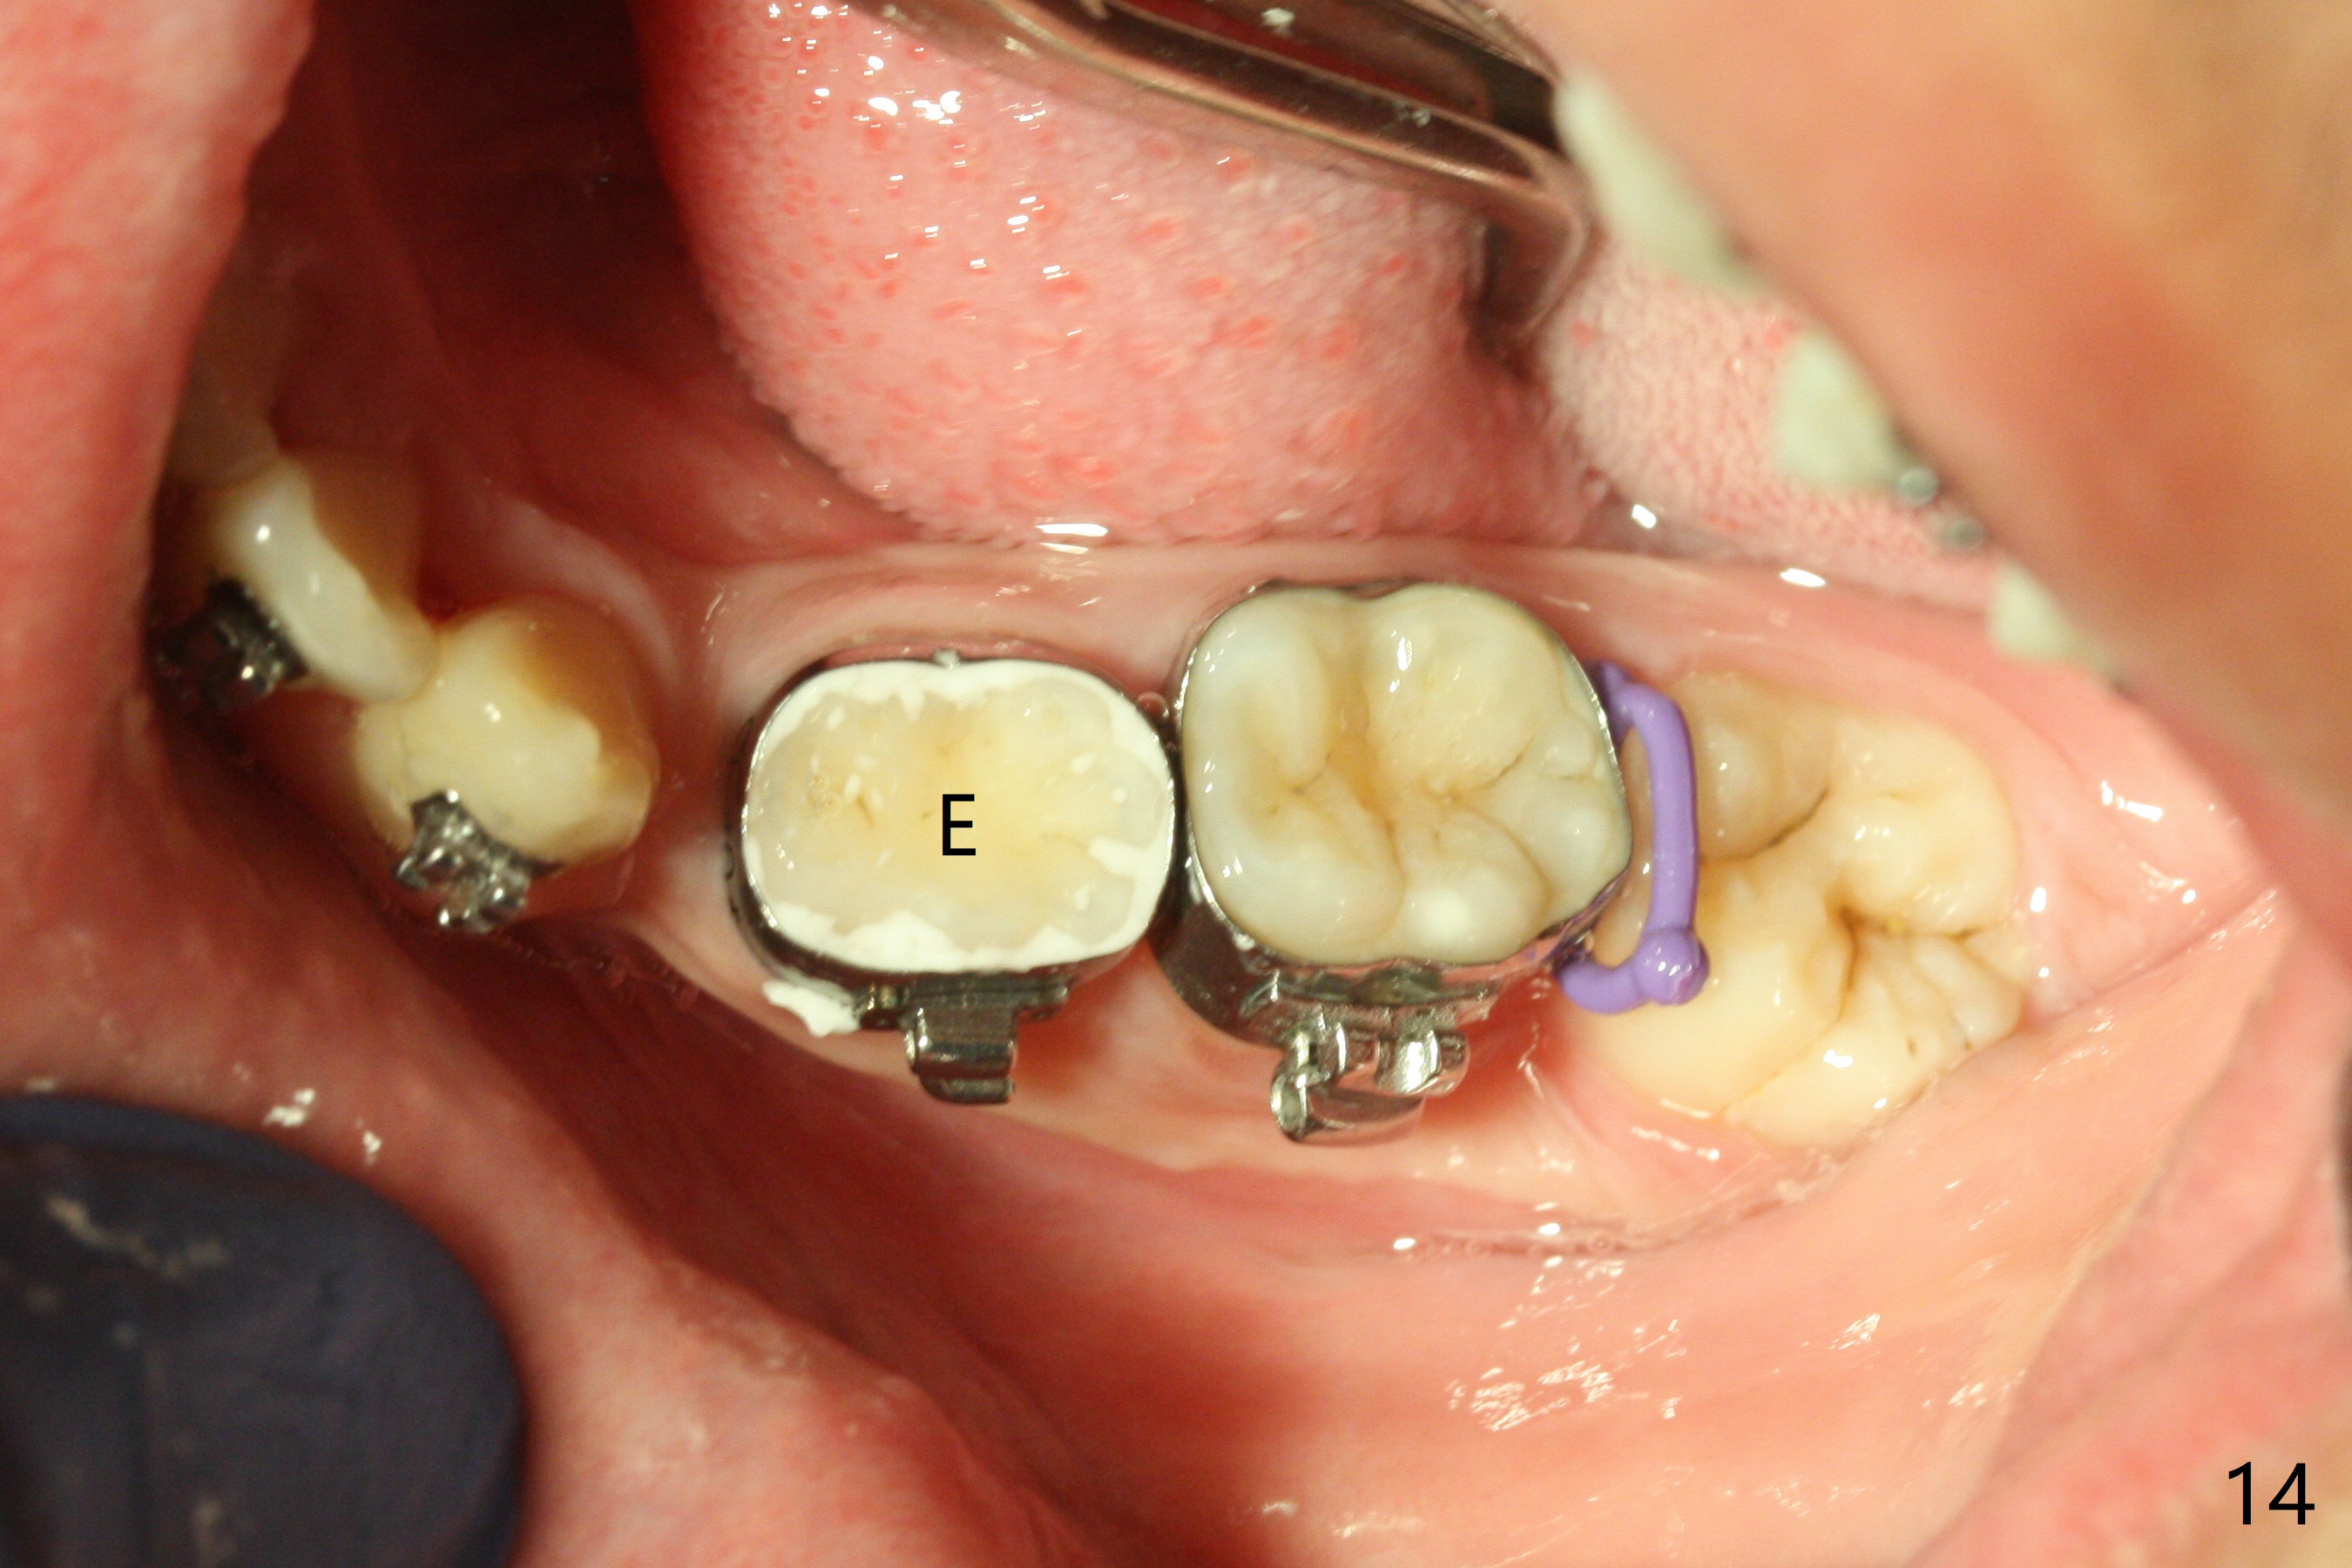

Eight months post banding, the interdigitation on the right side seems to be within normal limit (Fig.10), while the lower dental midline appears to be deviated to the left (Fig.11) with anterior overjet (Fig.12). The left canines remain Class II; open coil spring is placed between LL3-6 with intention to reduce anterior overjet and correct the lower midline deviation (Fig.13). Four weeks later, LL3 does not seem to be mesialized. It appears that the long open coil spring between LL3-6 is not effective. A molar band is added to LL E (Fig. 14,15). When a molar band is placed in LL7, an upper niti wire will be placed in the lower arch to expand the arch. When arch wire turns into thicker one, place open coil spring between LL3 and E.